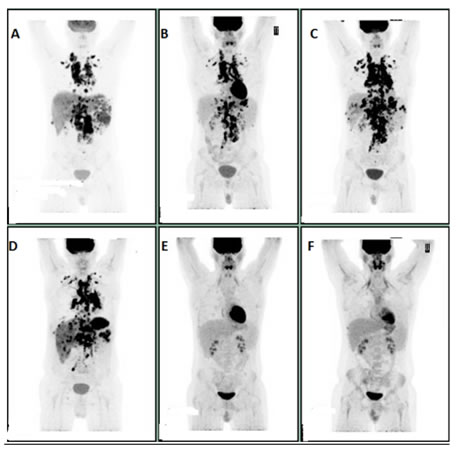

A 21-year-old male presented with persistent cough, weight loss, night sweats. PET scan in February 2016, showed intensely FDG avid lymphadenopathy in the lower neck, supraclavicular, chest and abdominal regions strongly suspicious for lymphoma. Left supraclavicular lymph node biopsy confirmed T cell rich B cell lymphoma and he was started on R-CHOP (Rituximab, Cyclophosphamide, Daunorubicin, Vincristine, and Prednisone). PET scan after five cycles of R-CHOP showed progressive disease on both sides of the diaphragm. The treatment was subsequently changed to Nivolumab on July 2016 and repeat PET scan in September 2016 after five cycles of Nivolumab revealed mixed response. The scan showed a considerable amount of FDG avid lymphadenopathy on both sides of the diaphragm. Some of the previously noted osseous lesions were improved, but there was more prominent involvement of liver, spleen and pleural and pericardial effusions were noted. Given concern for Nivolumab induced pneumonitis, Nivolumab was held, and the patient was started on prednisone in September 2016. He had a pericardial window and pathology from biopsy was positive for T cell rich B cell lymphoma. Patient was then started on salvage GDP (Gemcitabine, Prednisone, and Cisplatin) by the end of September 2016. A Pet scan after three cycles of GDP in December 2016 showed excellent metabolic response with virtual complete resolution of previously noted nodal and extranodal lesions and pericardial effusion, however with persistent bilateral pleural effusions (Figure 6A-6F). He completed five cycles of GDP and is being evaluated for autologous transplant.

Figure 6: A: Initial scan in February 2016. B: In April 2016, after three cycles of R-CHOP. C: In June 2016, after five cycles of R-CHOP. D: In September 2016, after five cycles of Nivolumab. E: In December 2016, after three cycles of GDP. F: In May 2017, after five cycles of GDP